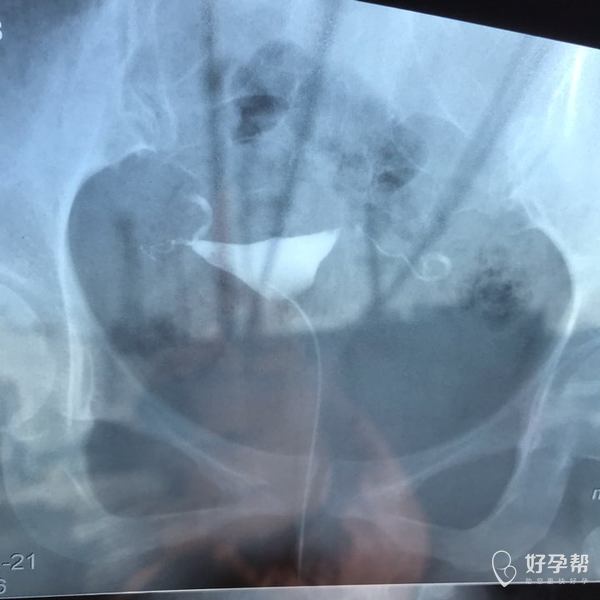

麻烦各位教授给我看看输卵管造影片子,谢谢了🙏

您好,输卵管堵塞,建议切除输卵管做试管,保守保守治疗没有多大意义,觉着我的回复对您有帮助记着帮忙点击采纳,谢谢!